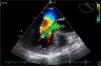

A 38-year-old female liver donor candidate was referred to our cardiology clinic for preoperative evaluation. The patient had no symptoms. On physical examination, a grade 2/6 early diastolic murmur was heard at the third left sternal intercostal space. Her blood pressure was 140/70 mmHg. Transthoracic echocardiography revealed moderate aortic regurgitation (AR) with the suspicion of quadricuspid aortic valve (QAV). Left ventricular end-diastolic and end-systolic diameters were 5.6 cm and 4.0 cm, respectively. Ejection fraction was normal. Transesophageal echocardiography confirmed the diagnosis of QAV with four equal cusps (Type A) (Figures 1 and 2, Video 1) with moderate AR (Figure 3). The patient was removed from the donor list with a suggestion for regular outpatient cardiology clinic visits.